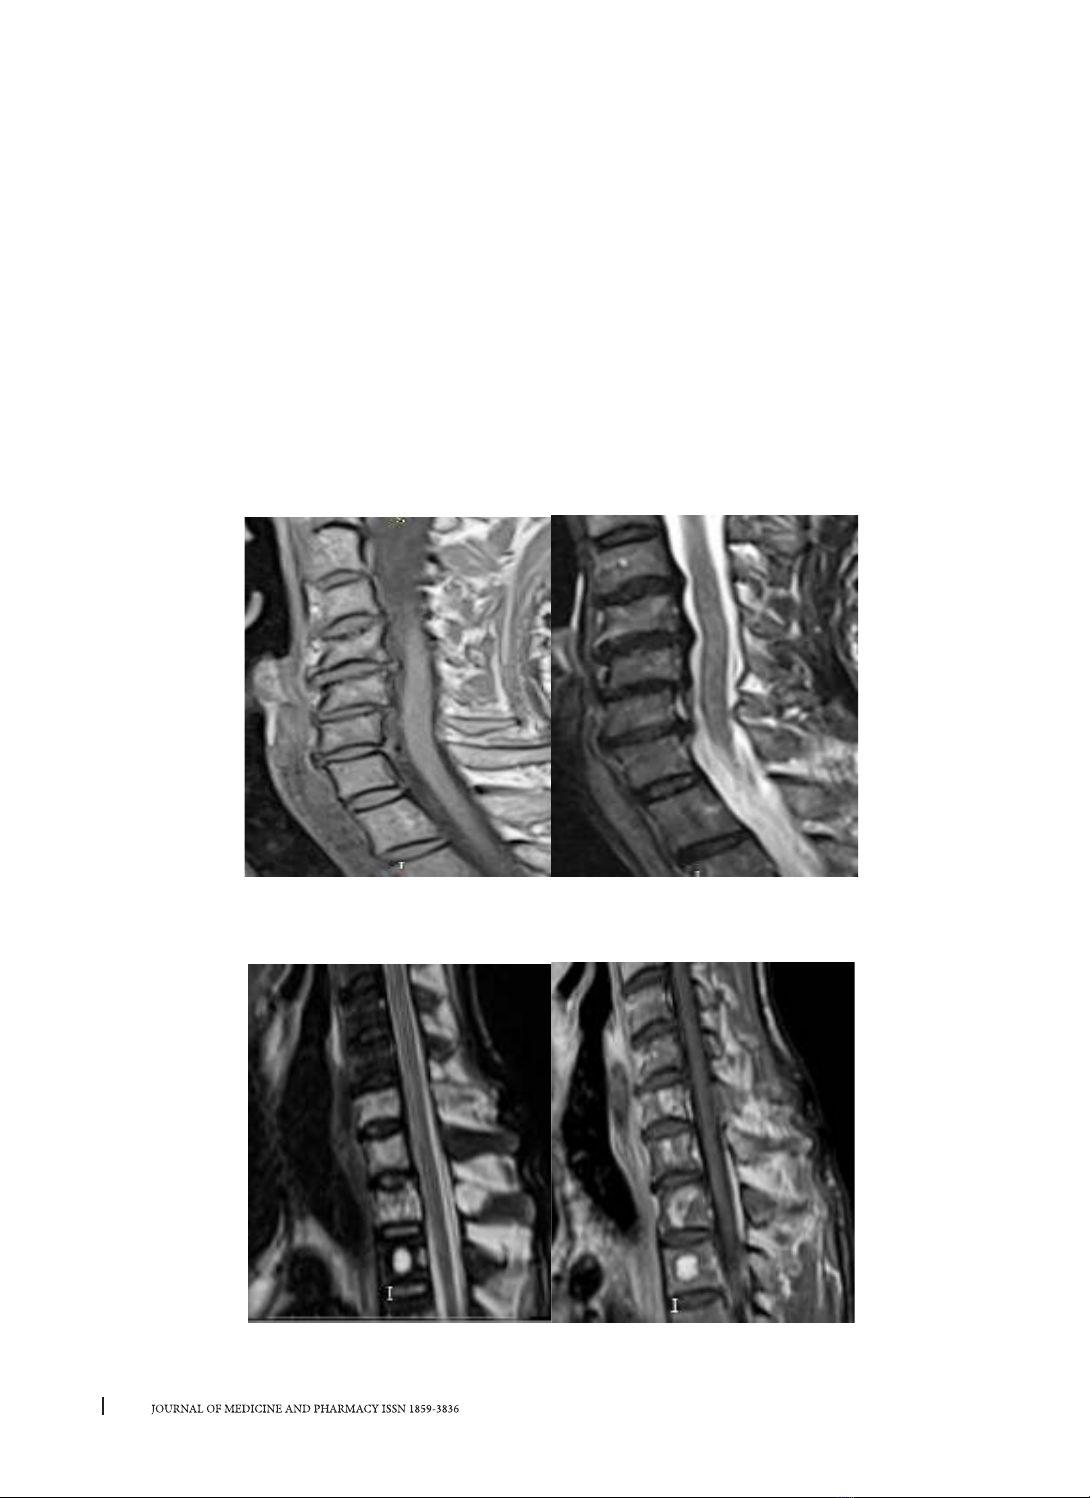

HÌNH ẢNH MINH HỌA

Hình 1. Hình ảnh trên chuỗi xung T1W, T2W của bệnh nhân Võ Đình T.

được chẩn đoán hẹp ống sống cổ mắc phải do nguyên nhân phối hợp: thoái hóa đốt sống, thoát vị đĩa

đệm và trượt đốt sống.

Hình 2. Hình ảnh tổn thương thứ phát ở thân và cuống sống

trên chuỗi xung T2W, T1 Gado của bệnh nhân Phan Văn T.